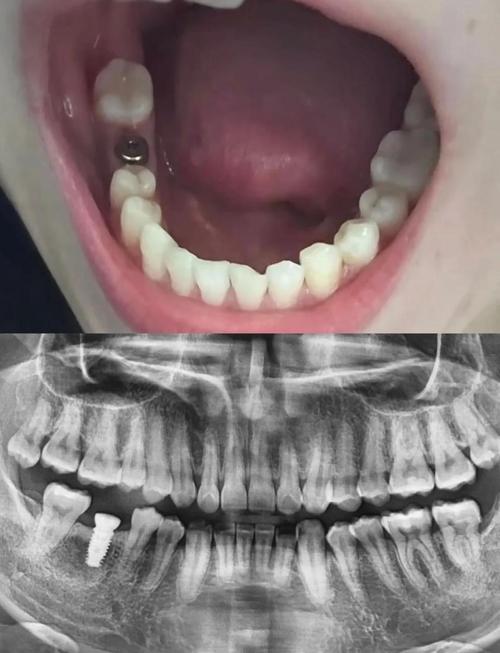

- 查看案例:要求医生展示过往类似病例的成功案例(如骨量不足患者的术前术后对比),直观判断其技术水平。